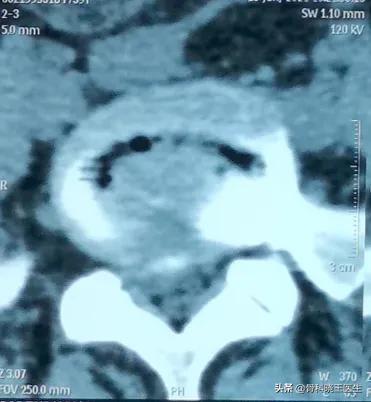

La hernie discale lombaire est principalement due à une mauvaise posture à long terme, à l'accélération des changements dégénératifs des vertèbres lombaires, des disques intervertébraux et des tissus mous lombaires, à diverses raisons conduisant à une fracture de l'anneau fibreux, à la saillie du nucleus pulposus, à l'irritation de la racine nerveuse, à l'ischémie et à l'œdème de la racine nerveuse, à des anomalies des fonctions sensorielles et motrices de la zone innervée. Les patients souffrant d'une hernie discale lombaire doivent-ils donc se reposer, et combien de temps doivent-ils se reposer ?

J'ai eu un accident de voiture une année, j'avais l'impression de ne plus pouvoir bouger, je suis allé à l'hôpital, on m'a fait un cliché et on m'a fait un scanner.